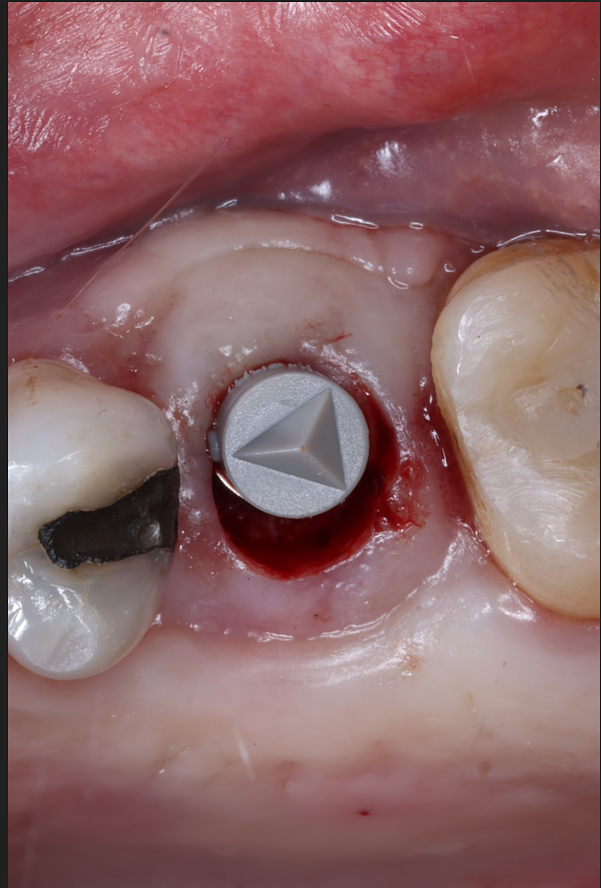

Today, we placed the implant, scanned for the final restoration, just like teaches us to do, and I placed a Neodent healing abutment.

Couple things about this case, I chose to do a tissue punch because the width of the ridge and the amount of attached tissue present. When we use the PTFE membrane for socket preservation, we ultimately grow nice, thick attached tissue, and this is a perfect example of that. I probably only do one or two tissue punches a year.